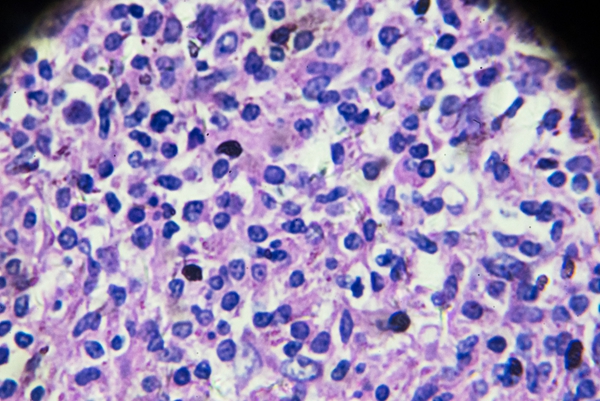

并发症:如果不及时治疗,HIV感染可能会导致各种并发症,如机会性感染、肿瘤等。这些并发症会严重影响患者的健康和生活质量,因此早期诊断和治疗非常关键。